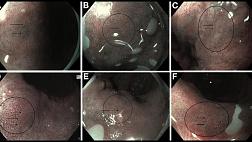

ШКАЛА EGGIM